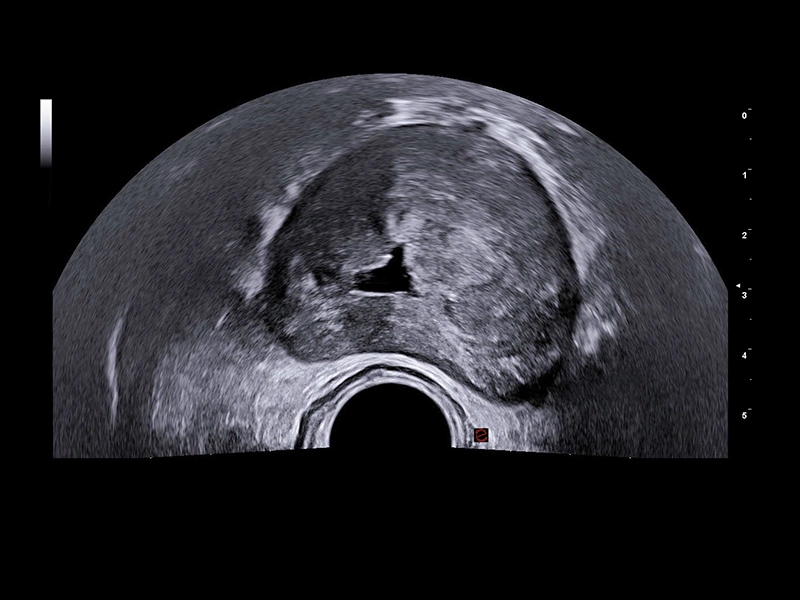

MyLab™9 Platform - Prostate contrast enhanced imaging (CnTI™)

MyLab™9 Platform - Prostate contrast enhanced imaging (CnTI™)